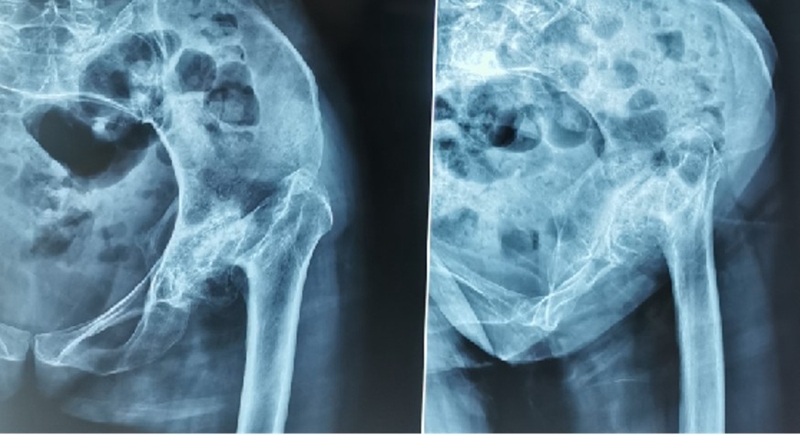

二、股骨近端畸形的分型---Berry分型

继发畸形多种多样,很少有病例与分型完全一致,但其核心要素是畸形位置和畸形类型。

畸形位置:大粗隆、股骨颈、干骺端、股骨干

畸形类型:成角畸形、旋转畸形、横行畸形、髓腔异常

冠状位:内翻、外翻

矢状位:前倾改变

轴位:旋转、长短

髓腔:变形、实变

Ⅰ、大粗隆畸形

(1)悬突型:大粗隆过度增生或移位,偏向内侧或前后方。

阻挡髓腔开口,内外旋时,大粗隆边缘与髋臼发生撞击;根据髓腔延长线开口,去除大粗隆多余骨质,去除大粗隆前后方骨赘,避免骨性撞击。

(2)高骑跨型:大粗隆位置高耸

大粗隆尖与髋臼边缘撞击,如果在肢体等长情况下,撞击仍无法避免,需要考虑大粗隆滑移截骨。

Ⅱ、股骨颈畸形---髋内外翻,offset异常

(1)颈干角偏小(<120°)——髋内翻

髋内翻,颈干角小,偏心距较大,选择high-Offset假体,以维持外展肌张力。

(2)颈干角过大(>140°) ——髋外翻

髋外翻多见于DDH,难度在于股骨距内侧皮质阻挡假体完全坐入髓腔,强行打击造成股骨距骨折。

Ⅲ、干骺端畸形

硬化骨、骨赘、骨质疏松、髓腔宽大

转子间骨折畸形愈合后常导致干骺端畸形,干骺端遗留大量硬化骨或髓腔成角,术中需在确认髓腔开口位置后,首选用小骨刀或高速磨钻去除硬化骨,打通髓腔。

干骺端畸形还可引起髓腔增宽,骨量减少,骨质疏松,不能为近端压配固定型的假体提供良好稳定。宜选用全微孔涂层远端固定假体。